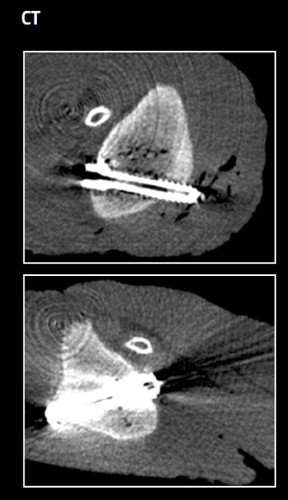

A new dimension in imaging

diagnostics

MAGNEZIX® screws and pins are metallic implants. Nevertheless, interference signals in computer tomography as well as MRT diagnostics are reduced to a minimum - the implants generate hardly any artefacts. This considerably improves the ability of surgeons and radiologists to assess the images. Moreover, unlike conventional products made of steel or titanium, MAGNEZIX® implants do not show any significant temperature increase during MRT.